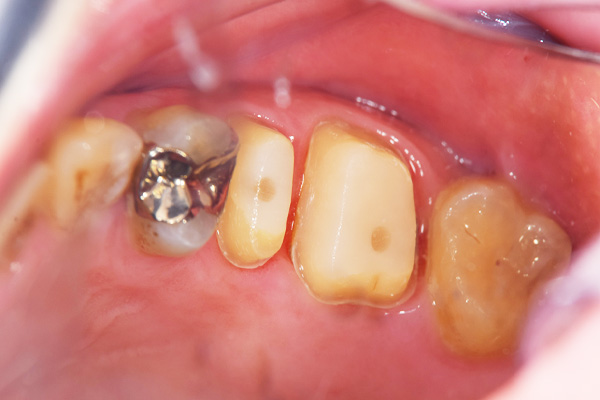

年齢・性別 40代・男性

主訴 左上の奥歯がしみることがある

治療内容 左上4の虫歯

治療期間 2週間

リスク・副作用 虫歯の大きさによっては、神経をとらないといけなくなることがあります。

また、虫歯が大きかったケースで神経を残した場合、治療後にしみるなどの

症状が続くことがあります。

費用 ・ジルコニアインレーで修復

55,000円

治療方針

IOSのNIRI機能によって虫歯部分が明らかになったので、虫歯を除去後に修復治療を行うこととしました。

特記事項

ラバーダムは歯とつめ物をくっつける際に非常に効果的です。

人間は呼吸をしますので、お口の中はかなり湿度が高くなっています。水が多い状態でものをくっつけようと思ってもなかなかくっつかないということと同じになります。

ですので、呼気中の湿度に左右されないようにするために、ラバーダムを用いて接着力を高くしています。

ラバーダムで息が苦しくなる場合は使用しませんし、ラバーのアレルギーがある場合も使用できません。

担当医師所見

虫歯の有無を確認する上で今まではレントゲンと自分の目での確認でした。現在は目で見るよりもはるかにわかりやすいIOSという装置がありますので、虫歯の発見がしやすくなりました。

そのため、患者さんの虫歯の進行の段階が早いうちにわかる様になり、神経をとらなければならないというケースが非常に少なくなっています。